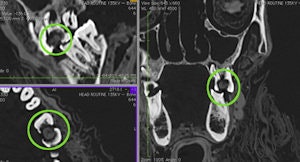

Multiplanar reformatted CT slices showing the packing material in the large interproximal carious lesion. Image courtesy of the International Journal of Paleopathology.','dvPres', 'clsTopBtn', 'true' );" >

| Multiplanar reformatted CT slices showing the packing material in the large interproximal carious lesion. Image courtesy of the International Journal of Paleopathology. |

The researchers also identified the mass previously found by Dr. Langsjoen in the carious lesions of the left first and second molars, and described it as a low-density, homogeneous ball of material, such as linen. It measures 7.7 x 7.1 x 3.7 mm, larger than the lesion's opening of 5.5 x 6.8 mm, but it remains loose within the cavity, they noted.